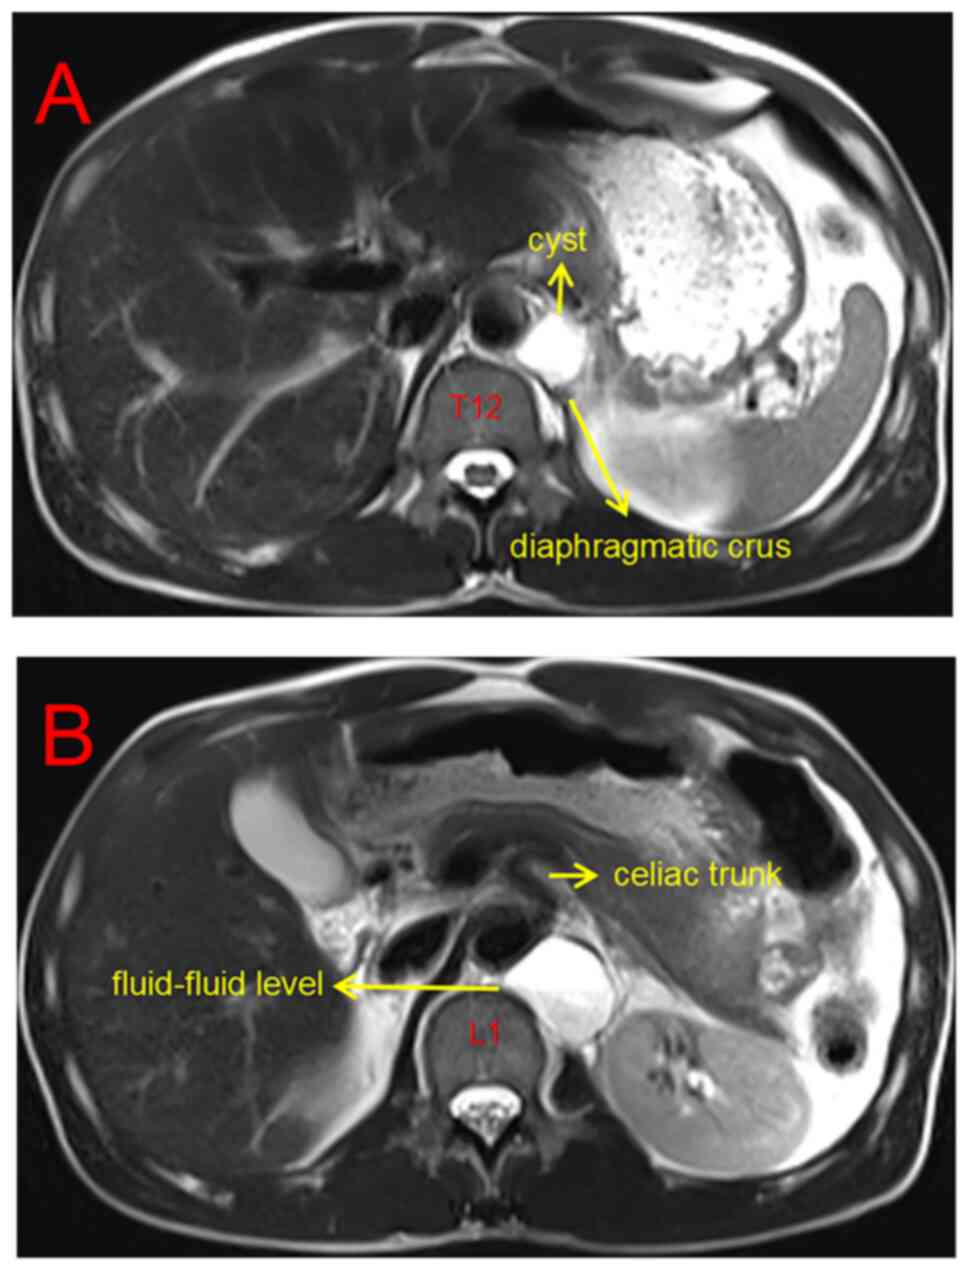

tube voltage, 120 kV; tube current, 200 mA. An MRI scan (Siemens

Magnetomveri 3.0T; Siemens AG) revealed that the cyst originated

from the left diaphragmatic crus, close to the spine and abdominal

aorta, with a fluid-fluid level in the cyst (Fig. 2A). An enhanced scan indicated that

the fluid signal in the upper layer of the cyst was higher compared

with that in the lower layer (Fig.

2B). The contents of the cyst had no enhancement, whereas the

cyst wall was smooth with mild enhancement (Fig. 2B). The MRI scanning parameters were

as follows: Repetition time/echo time, 2,000 msec/96 msec; matrix,